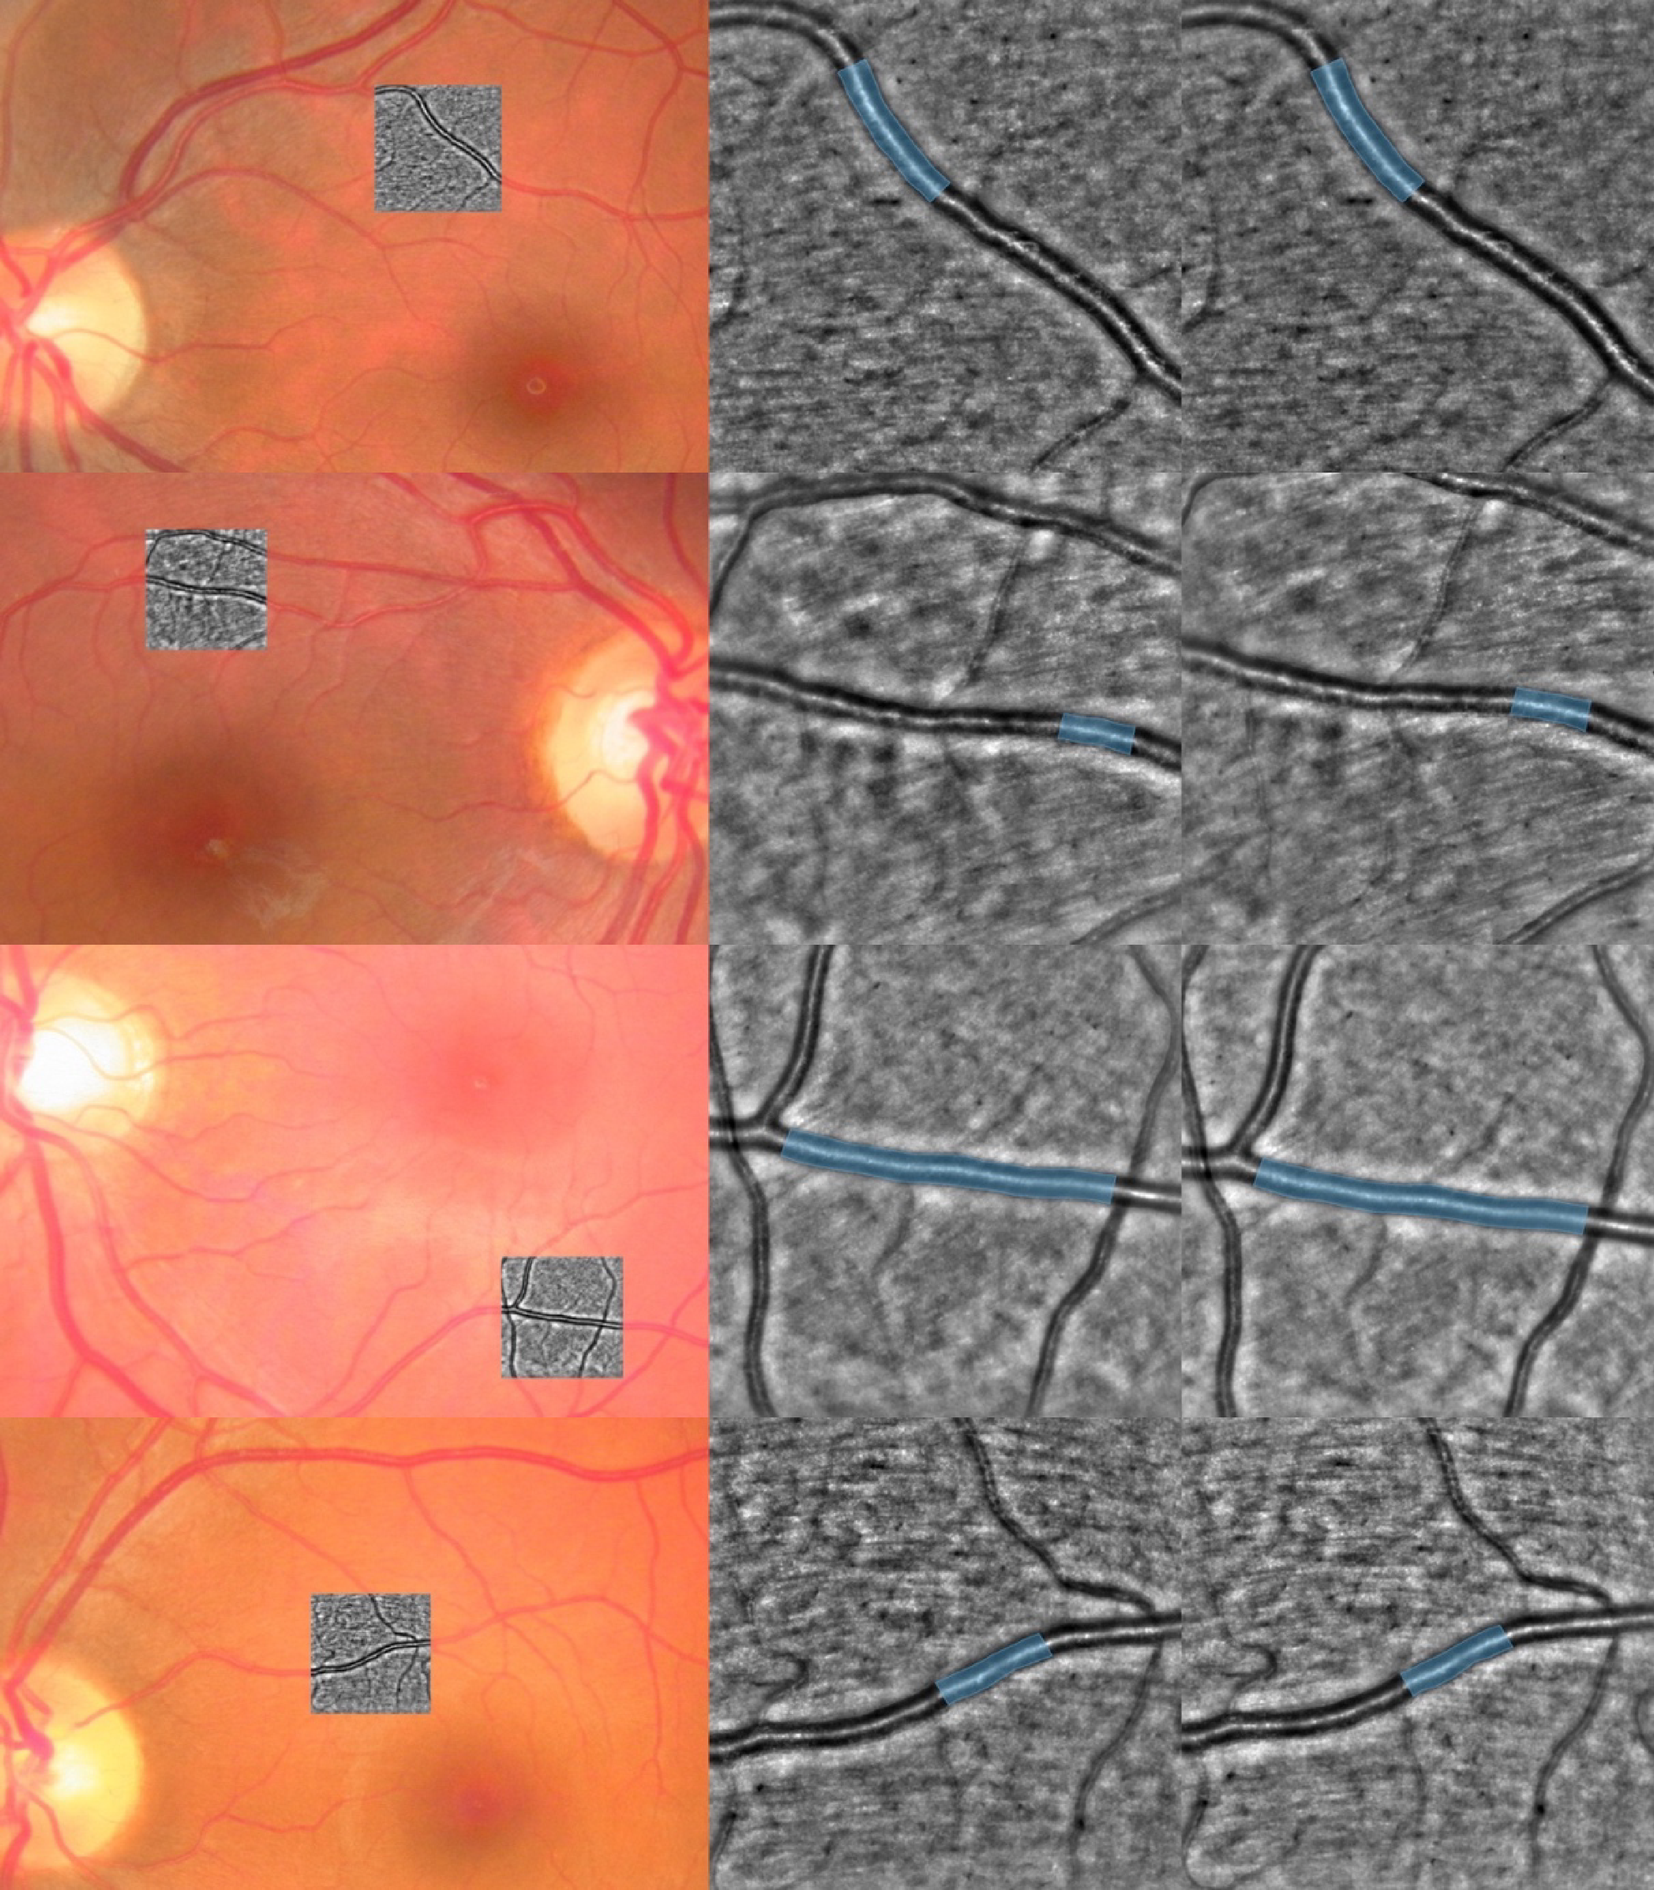

Fig. 3

Two healthy control (top) and two diabetic patients (bottom) examples. From top to bottom: cases HC03, HC08, DM02 and DM04. Left: color fundus photography with the rtx1 shown overlapped in grayscale. Middle/Right: full-size rtx1 images (4 × 4 degree field-of-view, 1500 × 1500 pixels) after the contralateral/ipsilateral stimulation. Analyzed vessel segment in blue. Additional example cases can be seen in the Supplementary figures.